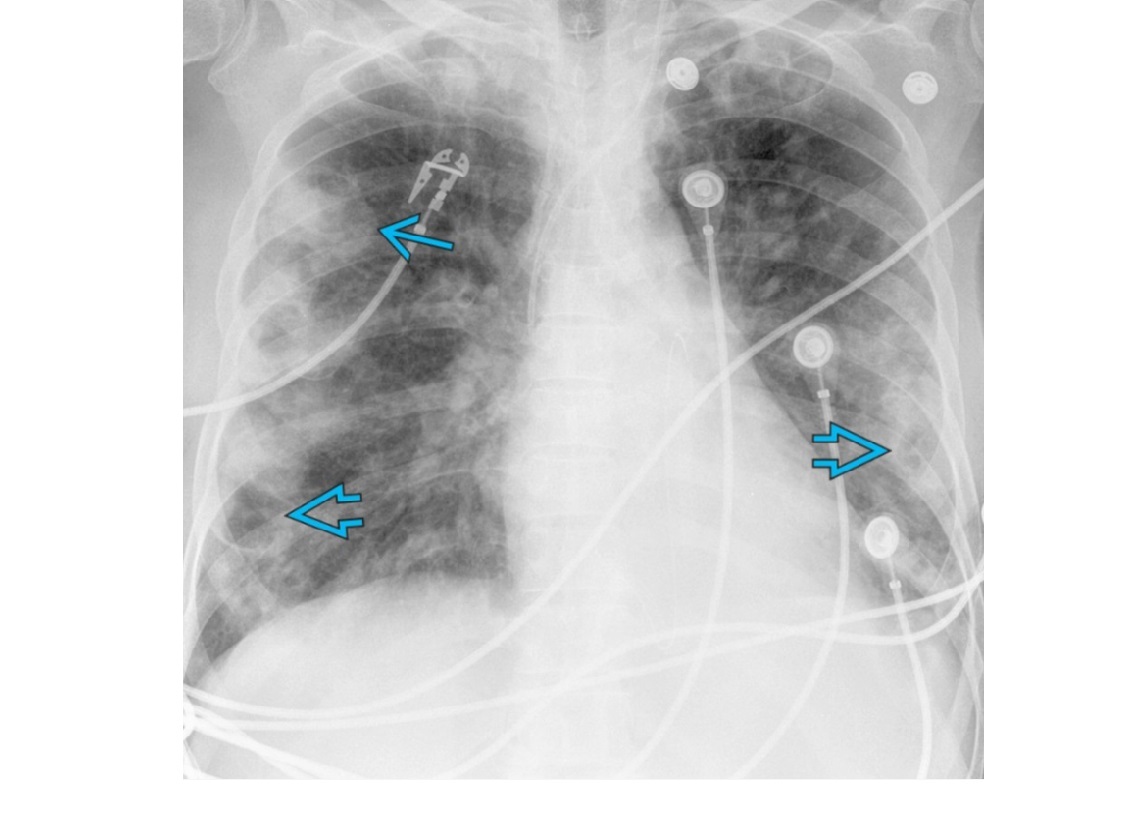

NSIP

lower lung zone predominant

CXR

bilateral, reticular opacities

CT

Absent (less) / microcystic honeycombing

Bilateral ground-glass &/or reticular opacities

Traction bronchiectasis/bronchiolectasis

Relative Subpleural sparing

peribronchovascular fibrosis

Most hunt for assocation/cause on CT

?dilated oesophagus - scleroderma

? joint disease - RA

?portcath/PICC - chemotherapy

sjorgens

HIV